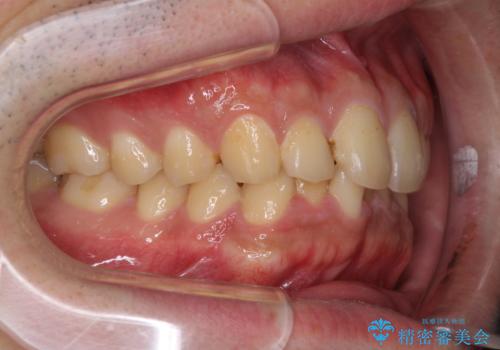

- 上下前歯のデコボコと下の前歯が隠れるほどの深い咬み合わせを気にして来院された患者様です。

インビザラインによる上下歯列の拡大と、IPR(歯と歯の間を削る)にるスペースの獲得により、口元のデコボコとディープバイトを改善することとしました。

デコボコがなくなったことで日頃の清掃が行いやすくなり、深い咬み合わせが改善したことで、食いしばりによる顎の負担も軽減されました。